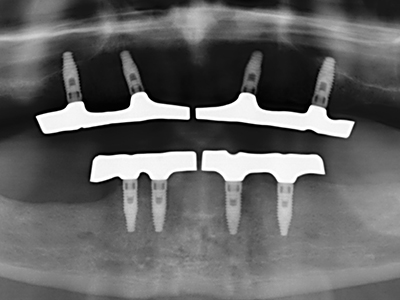

When surgical procedures are performed on bone in the immediate vicinity of sensitive structures such as blood vessels or nerves, rotary instruments pose a significant risk of iatrogenic injury. Piezoelectric devices can be helpful for preparation of bone covers and removal of hard tissue close to nerves, particularly for exposure of nerves after iatrogenic injury but also during nerve lateralization for resective and reconstructive procedures or implant placement (Fig. 17-20). Light contact between the piezotip and the nerve does not generally result in damage but proceeding incautiously with saw-like motions or attachments where a residual bone substrate remains may cause temporary or even permanent nerve damage. However, the risk of damage is considered to be substantially lower than when using saws or milling instruments (Pereira, Gealh et al. 2014).

As shown in the past, basically any bone surgery procedure represents a possible indication for piezo surgery. Thus preparation of the mobile segment in distraction osteogenesis (Fig. 23-25) and sandwich osteotomy uses special attachments without endangering the blood supply to the crestal section, which is essential for the success of both techniques (Gonzalez-Garcia, Diniz-Freitas et al. 2008).

Purely orthodontic indications include orthognathic surgery, genioplasty (Fig. 27-30) and orbital decompression in patients with advanced endocrine orbitopathy as a result of Basedow’s disease (Ponto, Zwiener et al. 2014). Piezo devices are also used in maxillofacial surgery and to remove tumours at the base of the skull in various hospitals.